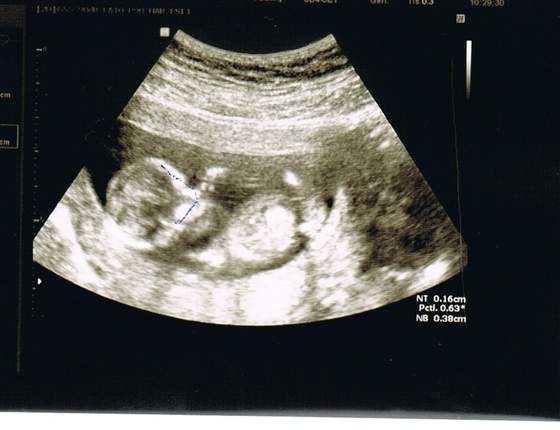

A tak w ogóle to śliczne zdjęcia. Rosną te nasze dzieciaczki. Nie mogę się doczekać kiedy ja znowu zobaczę moją kruszynkę.